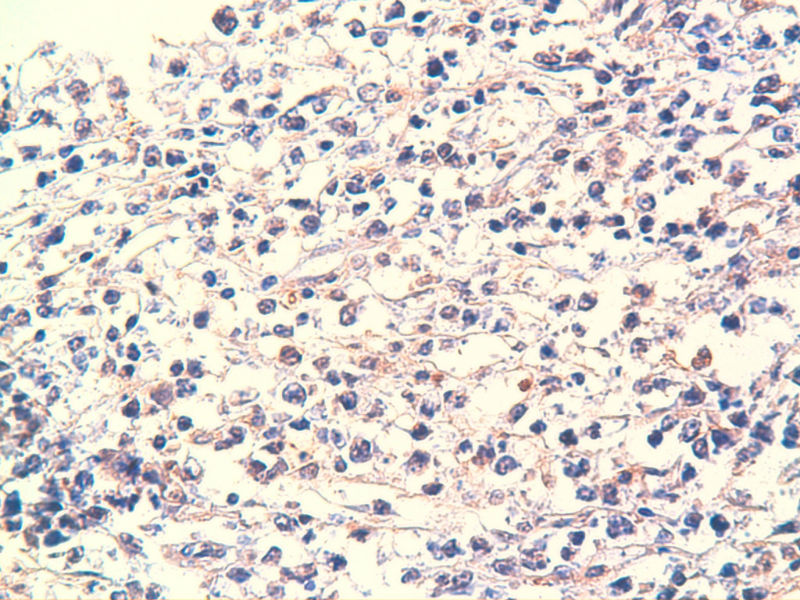

免疫组化染色:CA125(-),PLAP(-),NSE灶状阳性,Vimentin(+),a-inhibin(-),CK7(-),CK20(-),CD15(-),PSA(-),S100(-),MyoD1(-),CD38(-),CD56(-),HMB45(-),CK8(-),NF(-),CGA(-),syn(+),MPO散在(+)可能是炎细胞吧,LCA(+),CD133(+).

是的,syn(+),LCA(+), CD79a阳性, CD3阴性,NSE是局部胞核,胞浆着色,主要是胞浆着色;SYN也是局部,主要是胞核着色,胞浆很少。不对吗?我也迷糊。也许我看错了,不像那种典型的胞浆颗粒状着色。大家帮看一看。

今天又做了免疫组化,请大家帮看看。CD10(-),CD138(-),CDX2(-),CD3(-),CyclinD1(-),CD2(-),CD117(-),CD7(-),CD30(-),CD23(-);CD20强(+),BCL-2,Bcl-6,EMA,PAX-5,MUM-1,CD5,ALK,CD68都是散在阳性,大家帮确定一下是否阳性。B细胞淋巴瘤可以确定了,不知是哪种类型的?